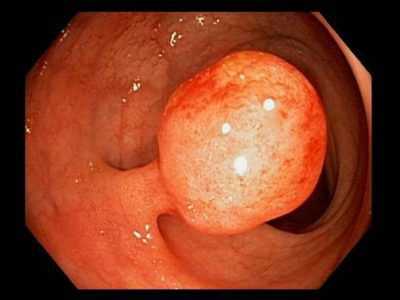

- Железистые (аденоматозные) полипы толстой кишки. Являются самым распространенным видом полипов, обнаруживаются у половины больных. Представляют собой плотные розоватые или красноватые гиперпластические разрастания железистого эпителия, обычно грибовидной формы, реже – ветвящиеся, стелющиеся по слизистой оболочке. Средний диаметр аденоматозных полипов составляет 2-3 см. Образования не склонны к изъязвлению и кровоточивости. Могут малигнизироваться.

Единственным способом лечения является хирургическое удаление полипов. При небольших образованиях без признаков малигнизации возможно использование щадящих эндоскопических методик. Операция проводится во время колоноскопии. В кишечник вводят эндоскоп со специальной петлей, петлю набрасывают на полип толстой кишки, перемещают к его основанию и удаляют узел, одновременно осуществляя электрокоагуляцию кровоточащего основания. Вмешательство хорошо переносится больными и не требует госпитализации. Трудоспособность восстанавливается в течение 1-2 дней.